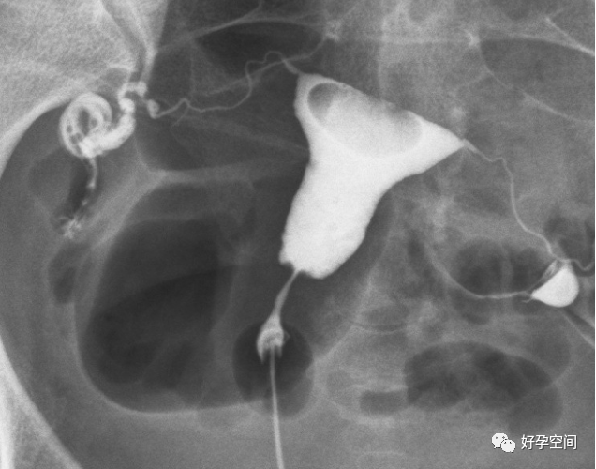

二、子宫输卵管造影正常

盆腔平片

子宫相

输卵管相